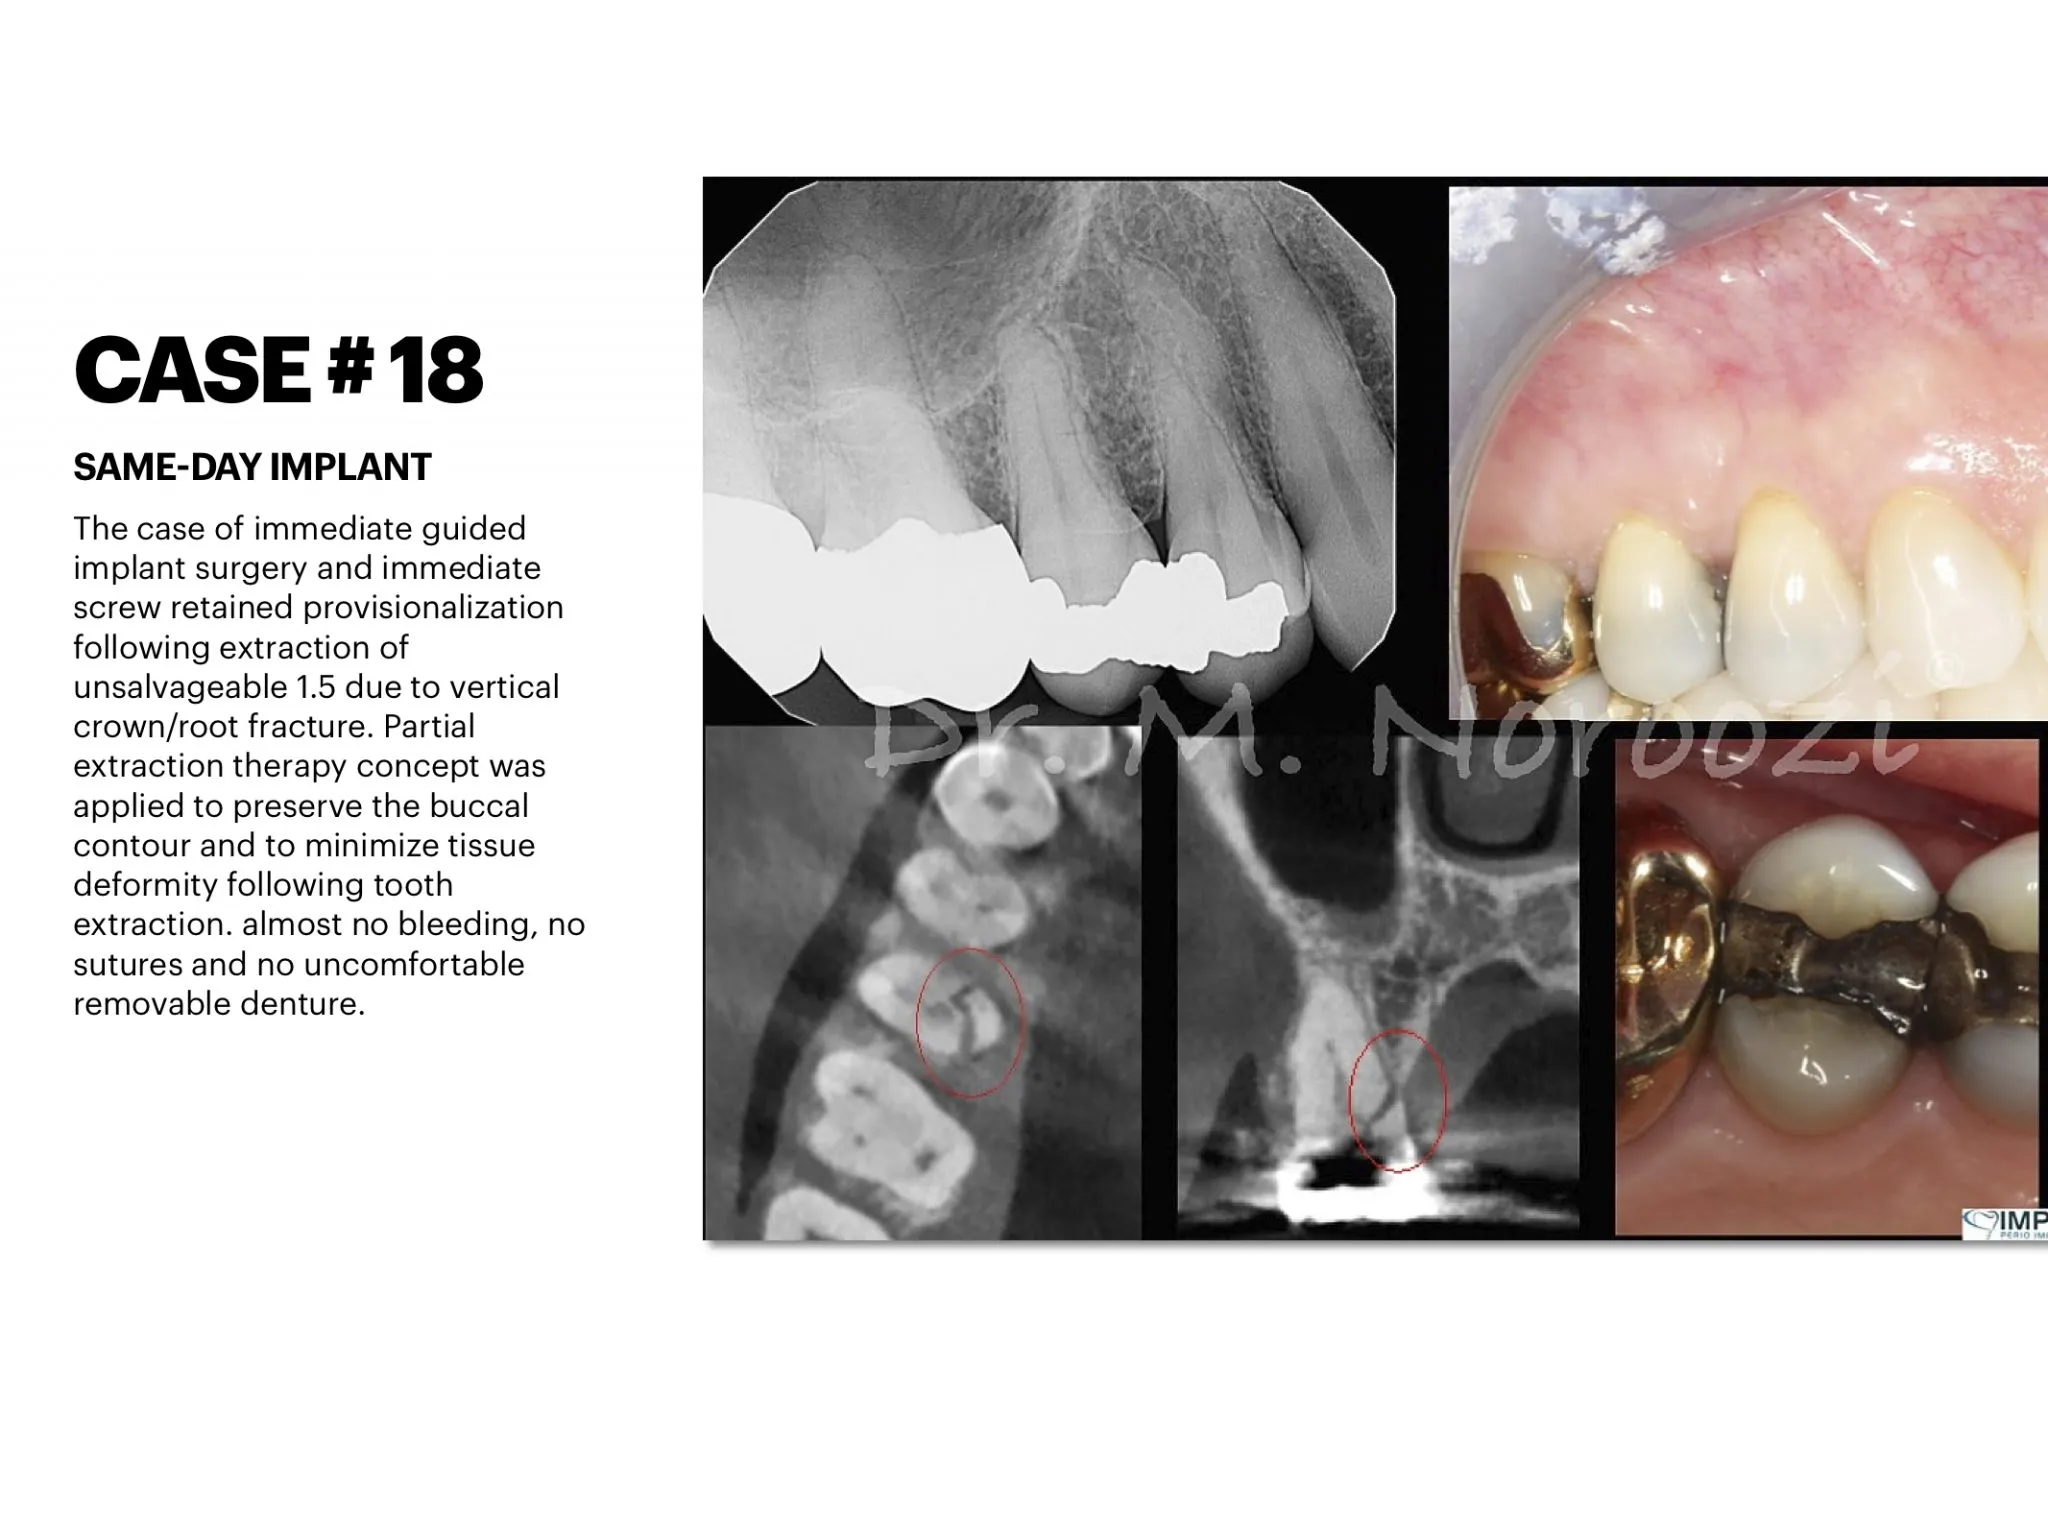

Surgical advances with SAME-DAY IMPLANTS in Vancouver BC

Using the most recent advances in dental implant technology, Dr. Noroozi is able to place single stage implants. These implants do not require a second procedure to uncover them but may require a minimum of six weeks of healing time before artificial teeth are placed. There are even situations where the implant can be placed at the same time as the tooth extraction and the artificial tooth can be inserted immediately following the implant placement – further minimizing your number of surgical procedures.

General Disclaimer: The results in the photographs are examples only and do not imply any certainty of the result of a procedure, and all outcomes are subject to the circumstances of the individual patient.